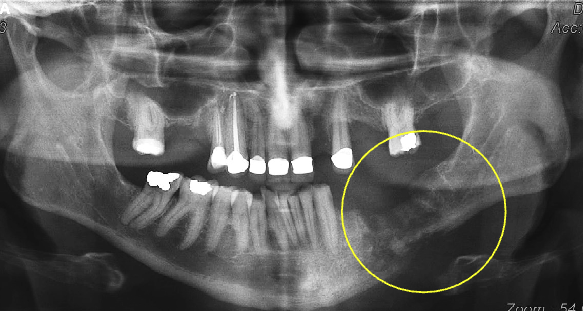

what’s the pathology of #7

apical rarefying osteitis

what’s the arrow pointing to

periosteal new bone formation

what are the arrows pointing to

“Halo sign”: elevation/displacement of max sinus floor